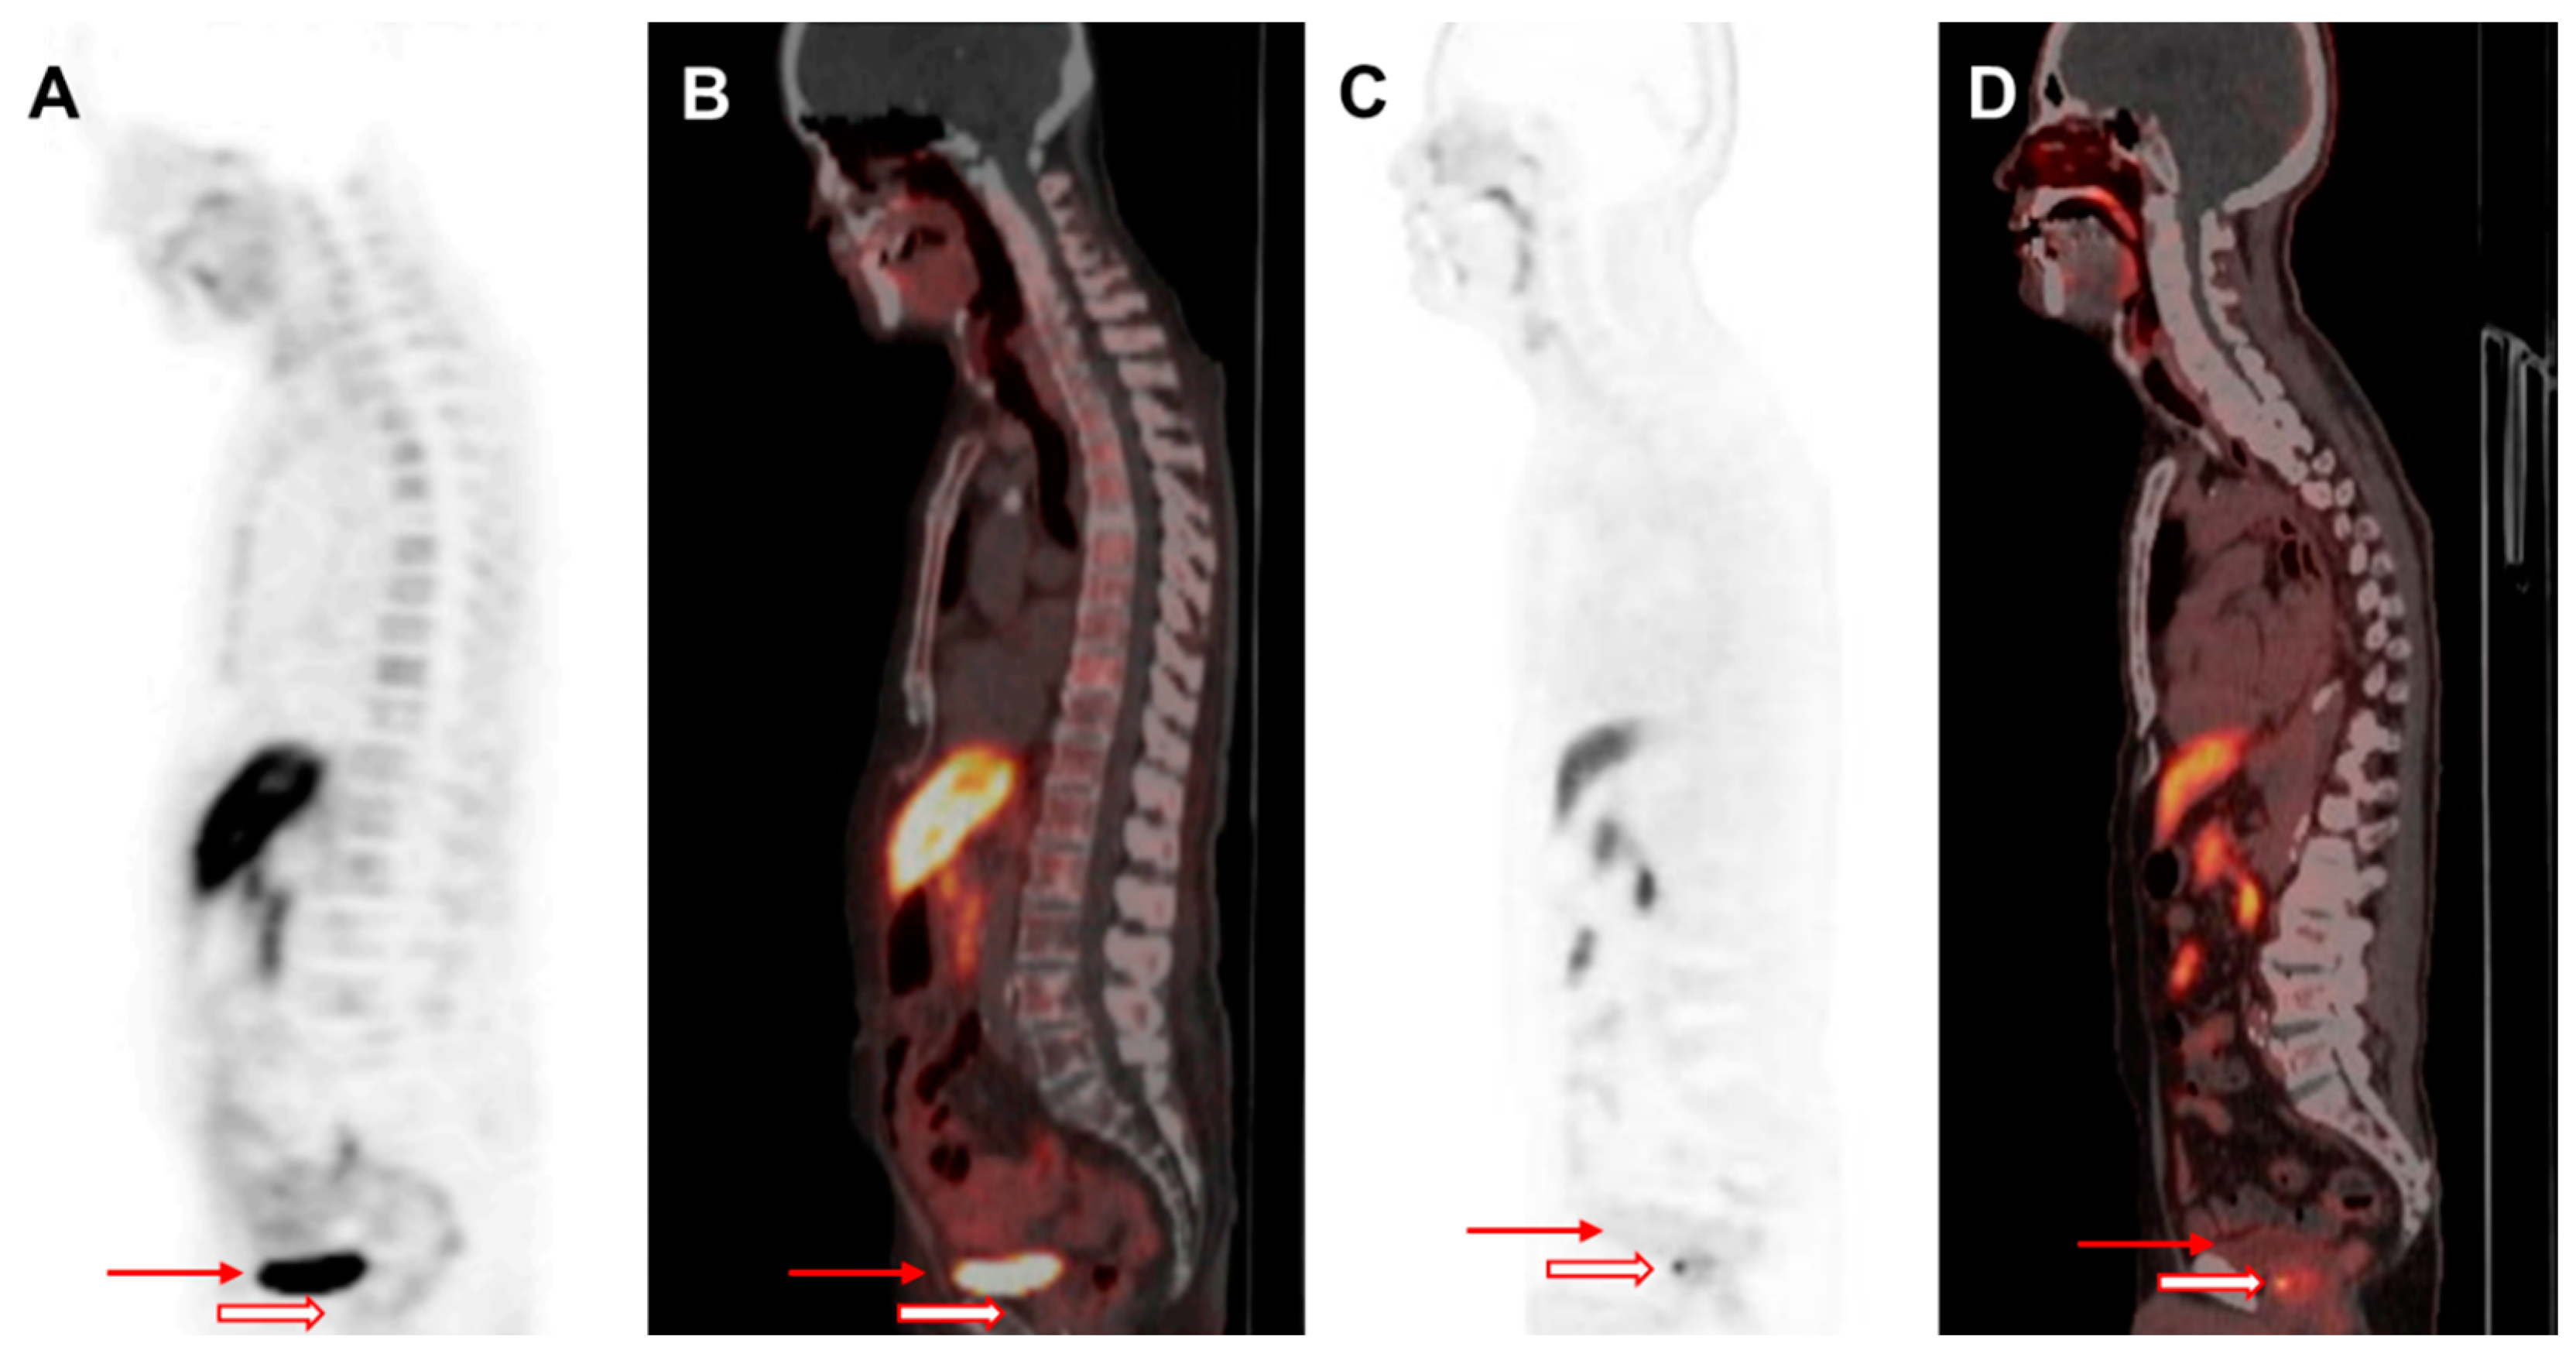

F-18 FCH PET/CT offers a significant advantage over C-11 choline PET/CT due to its longer half-life, making it more widely available for clinical use (Figure 2). Unlike C-11 choline, which is primarily used for bone metastasis detection, F-18 FCH has been approved for evaluating both soft tissues in cases of BCR or disease progression and for the early detection of bone metastasis, particularly when serum PSA levels exceed 1.0 ng/mL [5,32,33]. The increased choline metabolism observed in tumor cells is linked to enhanced phospholipid membrane synthesis and cell proliferation, which are indicative of biological aggressiveness in PCa [34,35]. F-18 FCH has demonstrated superior avidity compared with FDG in both androgen-dependent and androgen-independent PCa [36,37]. Despite urinary excretion, F-18 FCH PET/CT shows promise as a highly specific modality for primary tumor evaluation [38]. However, its clinical utility in PCa is limited by its low sensitivity, variable detection performance, and lower sensitivity as compared with that of PSMA-binding radioligand imaging [39,40,41,42]. The advent of F-18 PSMA-1007, which is excreted via the hepatobiliary system, has further reduced the role of F-18 FCH in clinical practice [5,43].

Figure 2.

Arrows indicate bladder activity, whereas empty arrows denote the prostate gland. (A,B) represent the FCH PET/CT images of a 74-year-old man with mCRPC who underwent docetaxel treatment, demonstrating an intense urinary tracer activity in the bladder. (C,D) correspond to the F-18 PSMA PET/CT images of a 70-year-old man diagnosed with PCa (Gleason score of 9). (C) F-18 PSMA PET and (D) fusion images reveal minimal bladder activity and focal radiotracer uptake within the prostate, corresponding to the areas of PSMA overexpression. Reduced bladder activity may enhance the evaluation of primary prostate tumors.